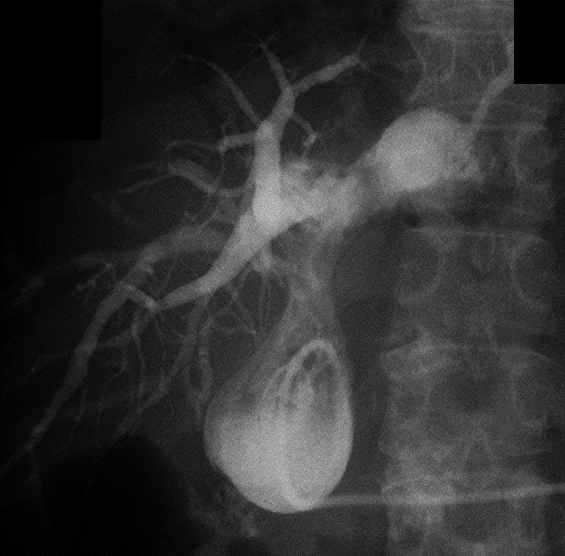

経過:繰り返す胆管炎の臨床的経過,および腹部造影CTでの挙上空腸の囊状拡張の所見から,挙上空腸に何らかの通過障害が疑われたため,ERCPを施行した.胆管空腸吻合部近傍の挙上空腸に狭窄を認めたものの,胆管空腸吻合部まで内視鏡は到達可能であった.胆管空腸吻合部には明らかな狭窄は認めなかったが,胆管空腸吻合部より盲端側の挙上空腸は著明に拡張し,腸管内に腸石,および胆石を認めた(Fig. 2a).以上より,挙上空腸の狭窄に伴う急性胆管炎の可能性を考え,挙上空腸内に内視鏡的胆道ドレナージ(endoscopic nasobiliary drainage;ENBD)用の6Frチューブを留置し,その後速やかに胆管炎は軽快した(Fig. 2b).しかし,ステント挿入1週間後にステント閉塞による急性胆管炎が再燃したため囊状拡張した挙上空腸を経皮的に穿刺ドレナージを行った.この時のドレーン造影では,拡張した挙上空腸内から肛門側腸管内への造影剤の排出は認められなかった(Fig. 3).ERCP施行時,胆管空腸吻合部から左右肝管二次分枝まで広範囲にわたって胆管上皮にびまん性の大小不同の顆粒状粘膜を認めており(Fig. 2c),さらに入院時の腹部造影CTを見直すと,挙上空腸の狭窄部は肝門部に集束するようにひきつれ,狭窄しており,癌による浸潤と考えた.また,肝十二指腸間膜内には腫大したリンパ節を認めた(Fig. 4a~f).左右肝管,および肝門部胆管上皮から生検を施行したところ,病理学的検査にて腺癌と診断された(Fig. 5a~c).以上より,切除不能肝門部胆管癌,T4aN1M0 stage IVAと診断した.

Infusion of contrast medium to the proximal jejunal limb identified dilatation, but the medium was not discharged to the distal side of the jejunal limb.